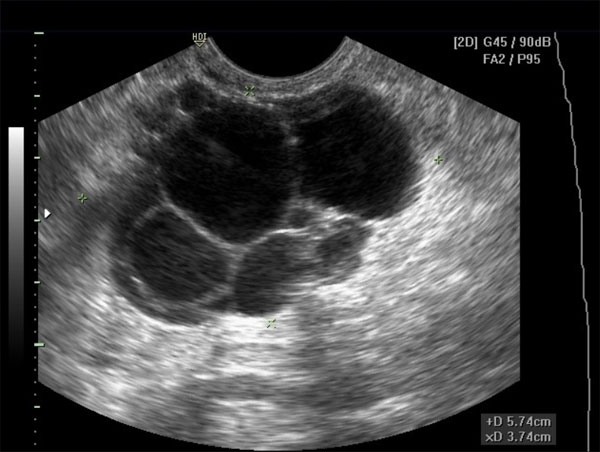

Polystic Ovary Syndrome

In this case the ovaries contain a large amount of small cysts.